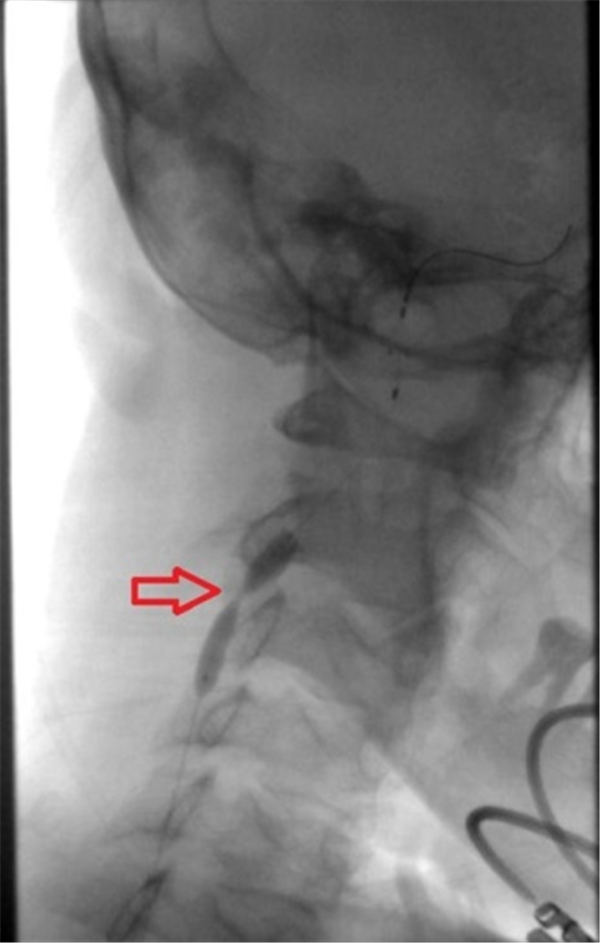

之后用球囊扩张右侧颈内动脉(上图红色箭头所示为狭窄部位)。